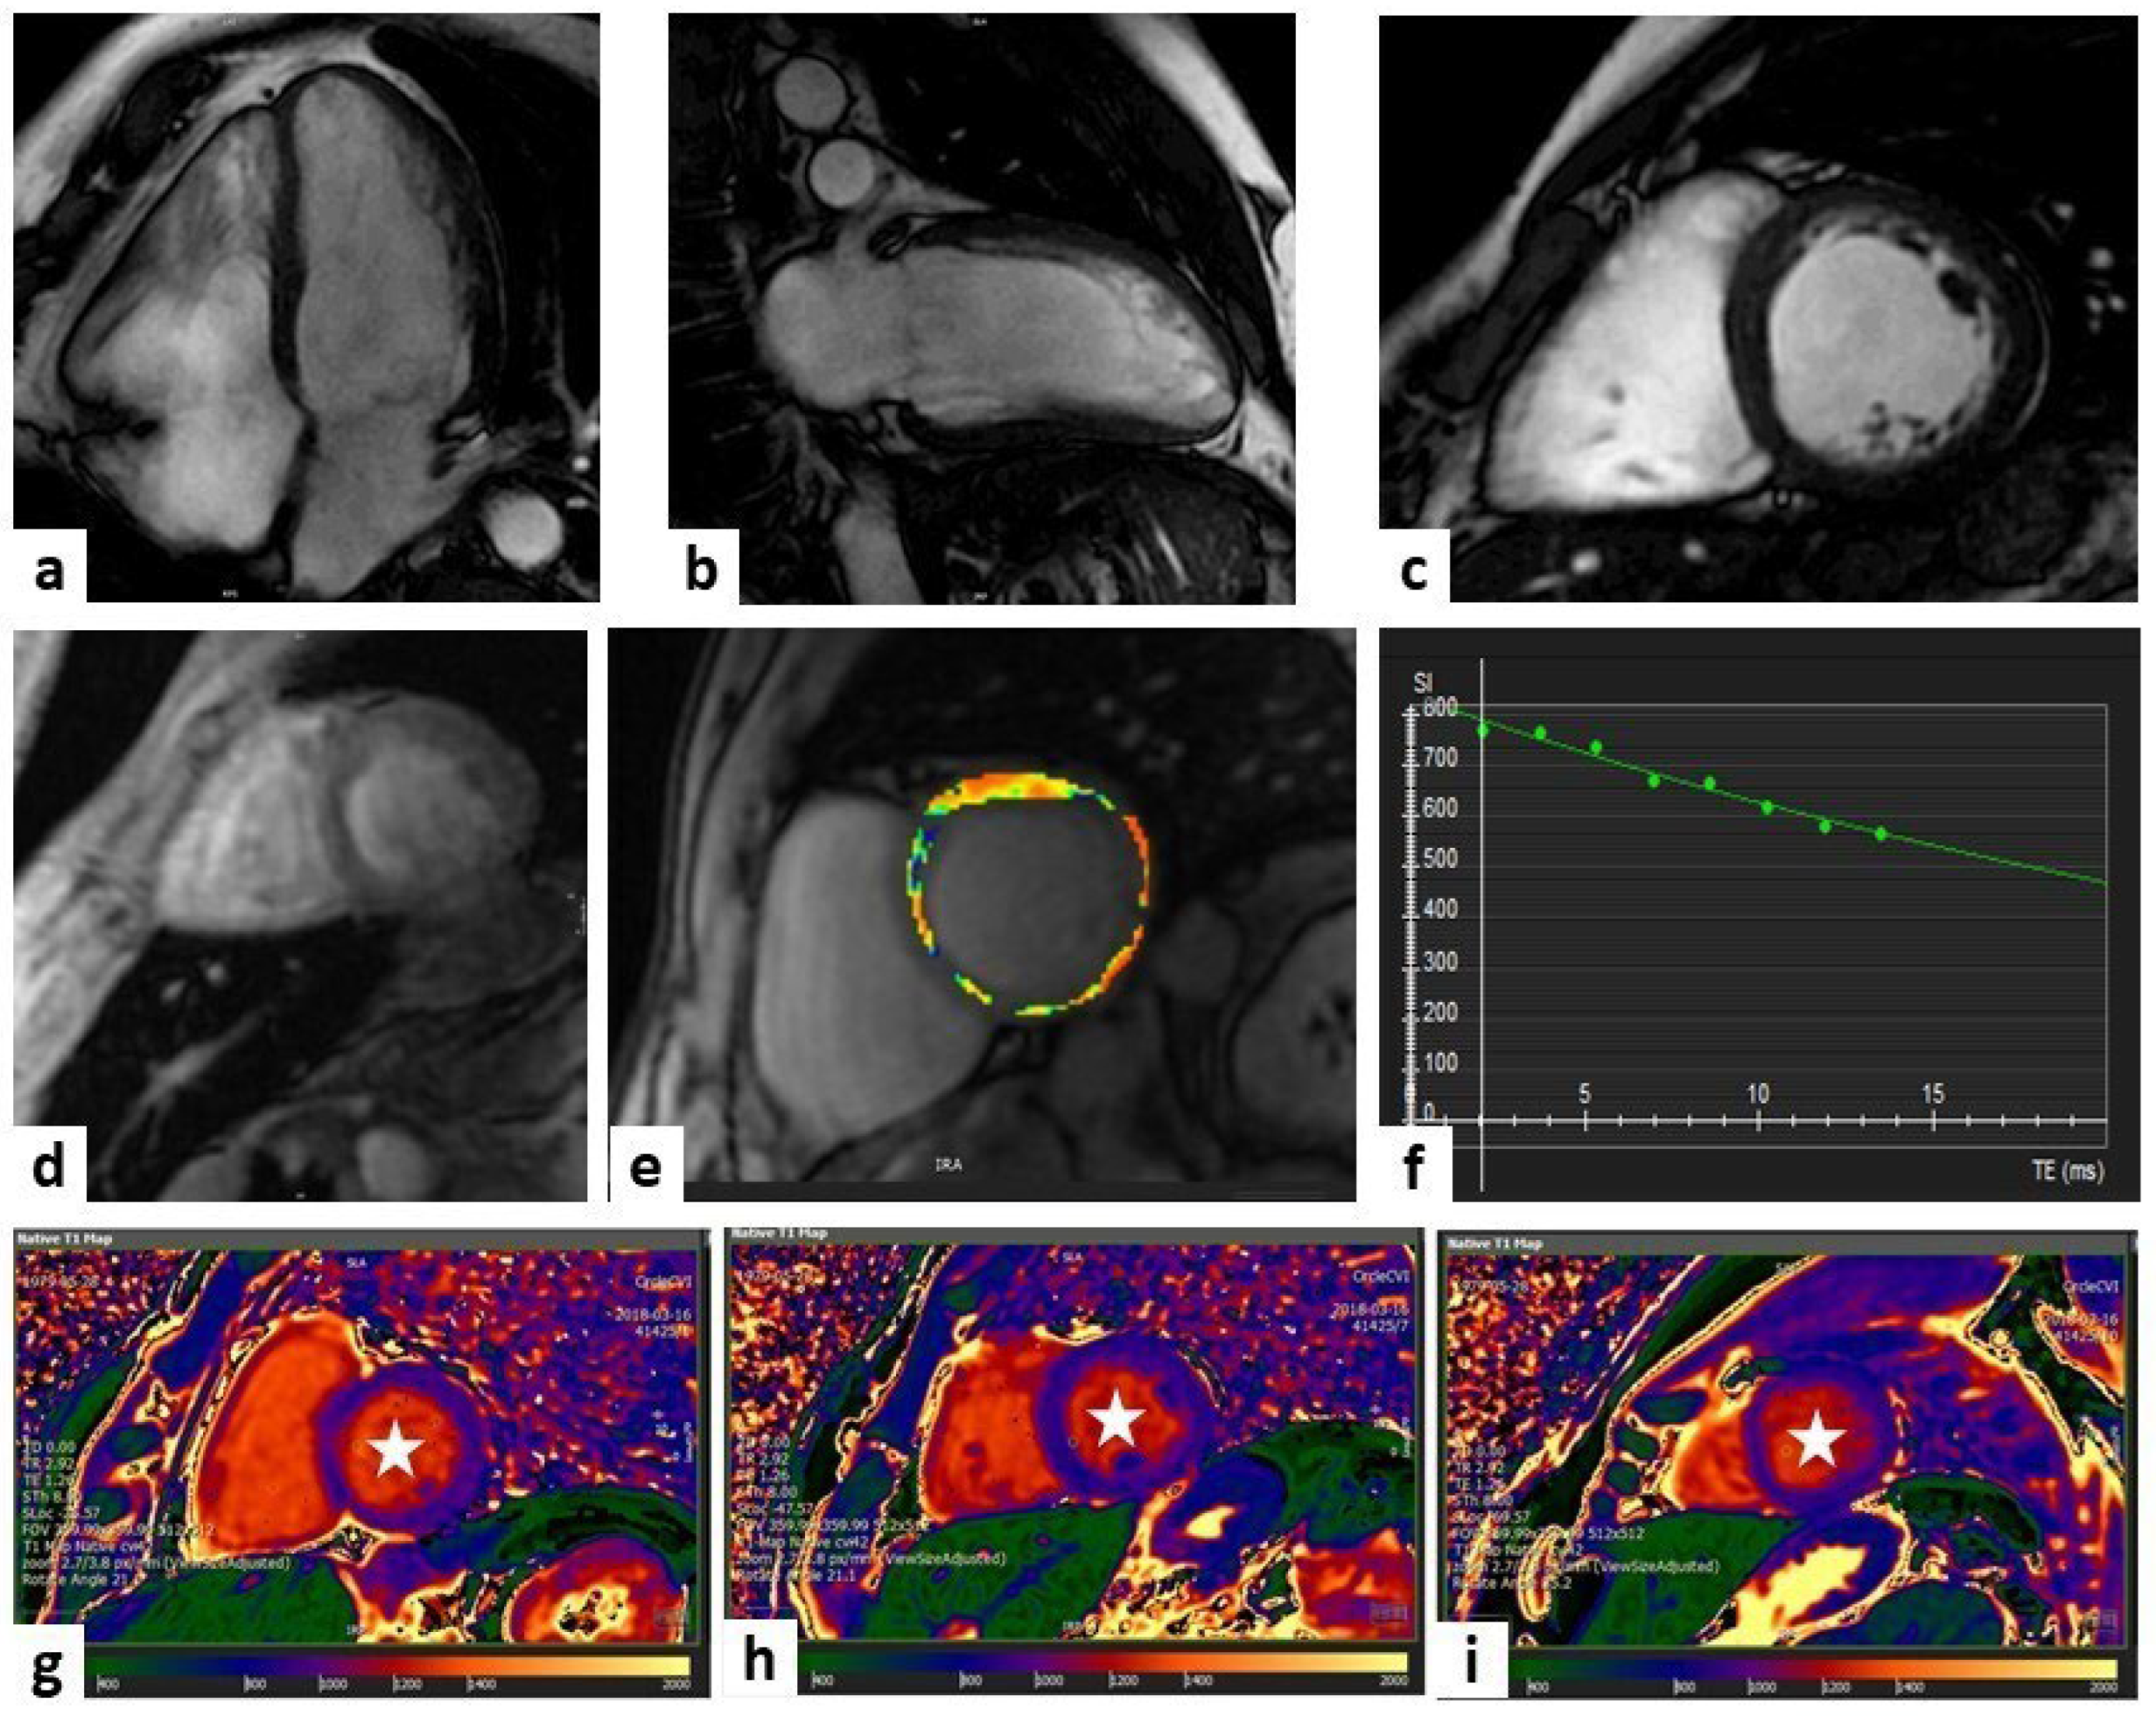

Postcontrast T1 mapping, which can be incorporated into standard LGE-CMR protocols, is useful to compute an ECV increase caused by amyloid infiltration (Figure 2). Recent studies demonstrated that high levels of ECV (ECV > 0.40%) can help to diagnose CA early on and are a prognostic sign in both ATTR and AL amyloidosis [56,57].

Figure 2.

Cardiac amyloidosis. A case of a 79-year-old man, with magnetic resonance imaging (MRI) showing a hypertrophic (white arrows) left ventricle (LV) of 17 mm in the steady-state free precession (SSFP) sequences (panels (a–c) show four-chamber, three-chamber, and two-chamber views, respectively). Mid panels show diffuse high values at T1 mapping sequences, represented by the orange tonality as indicated by the white arrows (panels (d,e) at the level of the basal and mid-LV short-axis views, respectively) and diffuse high values at extracellular volume (ECV) sequence, represented by the yellow tonality as indicated by the white arrows (panel (f) at the level of the basal LV short-axis view). Late gadolinium enhancement (LGE) sequences showed a non-ischemic enhancement pattern in both ventricles (white arrows), a hyperenhancement of the atrio-ventricular valves (red stars), of the left atrium wall and the interatrial septum (white arrowheads) (panels (g–i) show four-chamber, three-chamber, and two-chamber views, respectively). All these findings are diagnostic of cardiac amyloidosis.

T2 mapping is a noncontrast sequence and, as compared to T1 mapping, is more specific to detect myocardial oedema. T2 mapping values are increased in patients with both forms of CA, with a greater prevalence in AL than in ATTR.